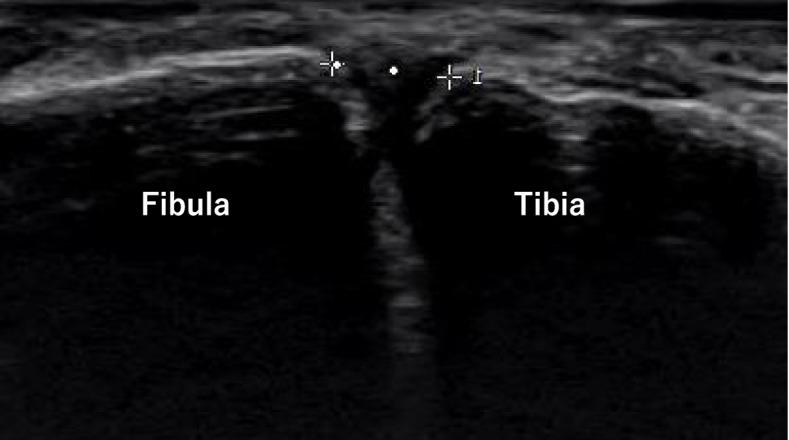

METHODS

Five normal ankles from Thiel-embalmed cadavers were used. Ultrasound assessment was performed by placing a probe in parallel with the ligament running just above the anterior inferior tibiofibular ligament (AITFL). The distance between the anterior border of the tibia and the fibula was measured in the intact condition. Next, Bassett's ligament was cut arthroscopically to reduce damage to soft tissues as much as possible and measurement was performed in the same way. After that, the AITFL, interosseous membrane (IOM), deltoid ligament, and posterior inferior tibiofibular ligament (PITFL) were macroscopically cut and measured in that order. Ankle positions were without stress (natural plantar flexion without applying stress to the ankle joint), dorsiflexion stress, inversion stress, and external rotation stress. All stress to the ankle joint was carried out manually to the maximum extent.

RESULTS

As with the without-stress condition, significant increases in tibiofibular distances after AITFL dissection were seen compared with the intact state under all stress conditions (intact: 4.9 ± 1.0 mm without stress, 5.6 ± 1.2 mm with dorsiflexion, 5.9 ± 1.0 mm with inversion, and 6.7 ± 1.3 mm with external rotation; AITFL dissection: 6.7 ± 1.5 mm without stress, 7.3 ± 1.2 mm with dorsiflexion, 7.5 ± 1.4 mm with inversion, and 8.7 ± 1.6 mm with external rotation). AITFL dissection with external rotation stress significantly increased the tibiofibular distance compared to without stress.

CONCLUSION

Changes in tibiofibular distance with the severity of syndesmosis injury were measured by ultrasound using cadavers. No significant change was seen with Bassett's ligament injury, but tibiofibular distance increased significantly with injuries of equal to or greater severity than AITFL injury. Results were similar not only for external rotation stress, but also for dorsiflexion stress and inversion stress, and even in unloaded states, significant tibiofibular widening was confirmed with injuries of equal to or greater severity than AITFL injury.